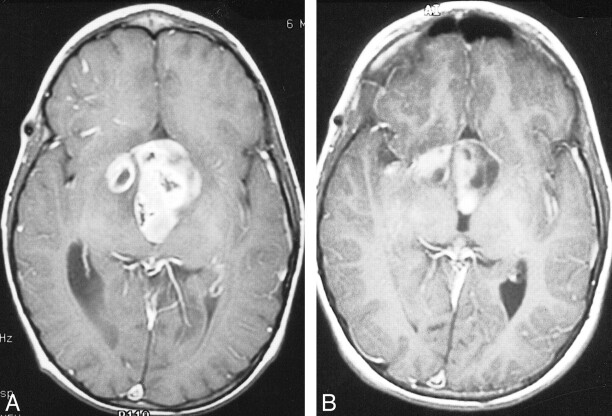

A 10-month-old male patient with right eye nystagmus was diagnosed by CT to have a partly cystic, partly solid, contrast-enhancing chiasmatic glioma. The patient underwent partial excision with histopathology of pilocytic astrocytoma and was treated with carboplatin and etoposide for four cycles. Eight months later, CT revealed tumor progression, and the patient was treated with vincristine and lomustine for a year. At that time, his right eye showed amblyopia and total optic atrophy. One year later, the disease had again progressed, and lomustine, procarbazine, and 6-thioguanine was administered for another year. Fourteen months later, evidence of progression was again revealed by MR imaging (Fig 1A) and visual field examination showed significant visual field loss in the left eye. At that time, the patient underwent combined intraarterial and IV chemotherapy. After the first procedure, the patient's platelet nadir was 15,000/mm3. For subsequent cycles, the carboplatin dose was reduced by 25%, and two further transfusions were required after the seventh and 12th treatments. After four courses, the visual fields showed moderate improvement and the monthly CT scans showed moderate but continuous decrease in the size of the contrast-enhancing region of the tumor. After completion of 12 cycles of chemotherapy, eye examination revealed improvement in visual fields. Three months after completion of chemotherapy, MR imaging showed partial response with further reduction in the solid part of the tumor (Fig 1B).

fig 1.

Images from the case of a 10-month-old male patient with right eye nystagmus who was diagnosed by CT to have a partly cystic, partly solid, contrast-enhancing chiasmatic glioma (case 1).

A, Contrast-enhanced axial view T1-weighted MR image, obtained after partial resection and three regimens of systemic chemotherapy, shows a strongly contrast-enhancing nodular suprasellar mass with an associated cystic component.

B, After 12 courses of combined intraarterial and IV chemotherapy, the volume of the solid tumor component and the degree of contrast enhancement are significantly decreased. There is no significant change in the volume of cystic component